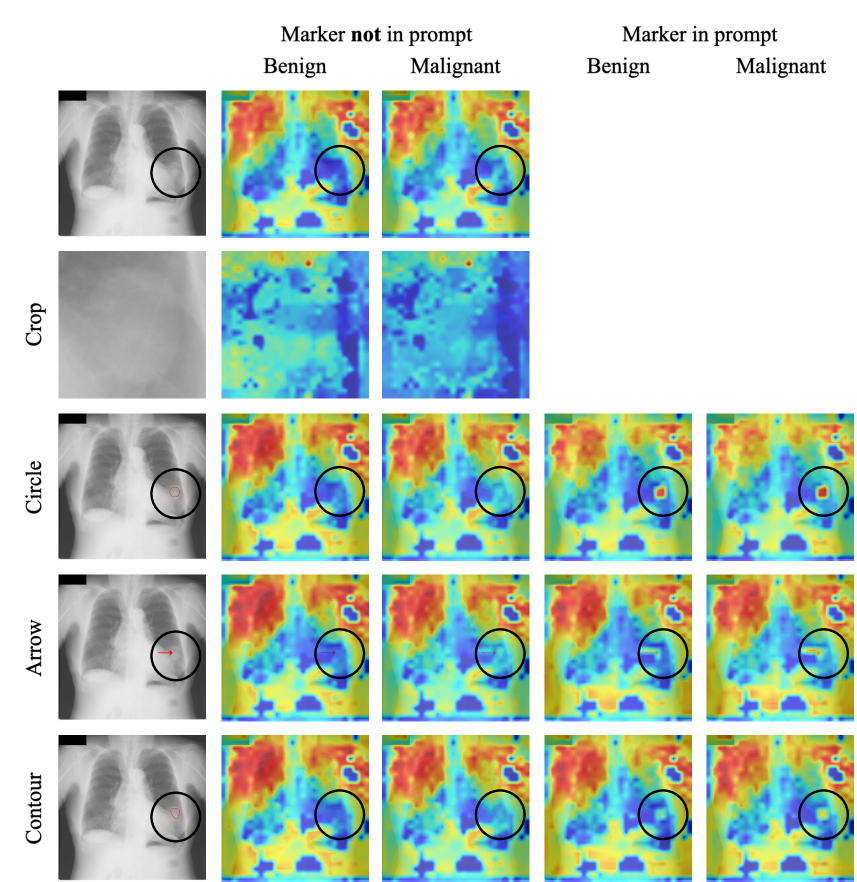

Refer to caption

Figure 3: Inputs and LeGrad attention maps of BiomedCLIP with different visual prompts. Each row presents a different visual prompt. The first column visualizes the different input images. The following columns visualize the LeGrad attention maps for the different classes and if the prompt technique was mentioned in the input prompt. Black Circle overlays are only for readers visual guidance and were not seen, nor produced by the model.

4.2 Explainability

To better understand the effect of adding visual prompts, we employ an explainability method, namely LeGrad [1]. The attention maps (visualized in Fig. 3) revealed that when visual markers were mentioned in the text prompt, the model’s focus was more aligned with the regions of interest. This suggests that visual prompts not only improve quantitative performance but also enhance the interpretability of the model’s decisions by ensuring it attends to clinically relevant areas.